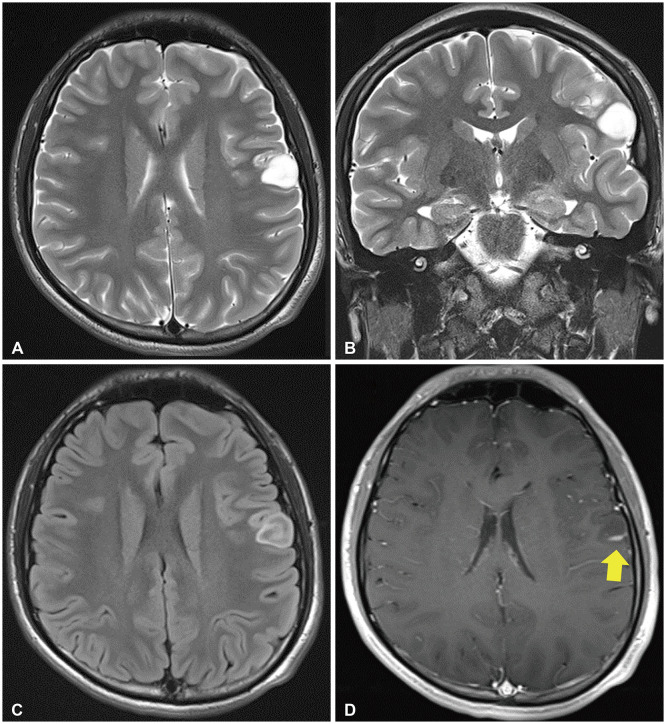

Angiocentric glioma (AG) is an extremely rare tumor that often develops in adolescents. Awake surgery for AG occurring in the eloquent area has not been reported to date. We report a case involving a right-handed 15-year-old boy with AG. He presented with a first-time generalized tonic-clonic seizure and was rushed to the local hospital. CT of the head indicated a left frontal low-density mass with no calcification. He was subsequently referred to our hospital. Comparison with a CT scan obtained two years prior due to mild head trauma indicated that the lesion showed a trend toward enlargement. The lesion was located in the anterior and lateral portions of the primary motor cortex, and MRI showed homogenous hypointensity on T1-weighted and hyperintensity on T2-weighted images. Contrast-enhanced MRI showed a linear contrast effect. The patient underwent awake surgery with successful intraoperative brain mapping and total resection, and brain function was preserved. Pathological analysis revealed AG. He returned to his normal life and has shown no recurrence without additional treatment for 2 years. Thus, awake surgery for complete tumor resection while preserving brain function is effective and safe even in adolescents with AGs.